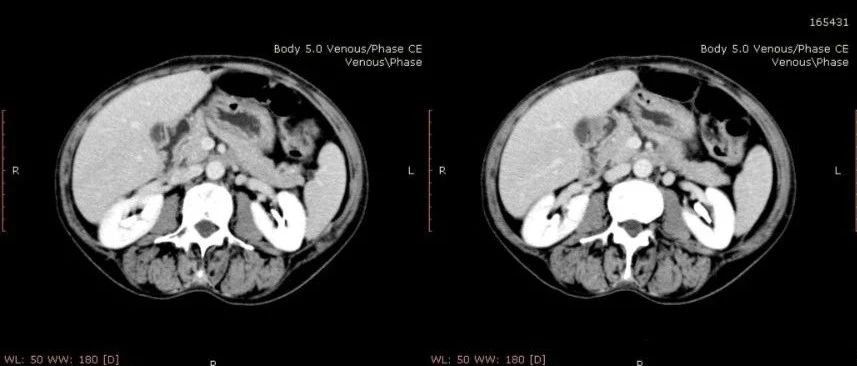

女性,活动后心慌气短十余年,颜面部肿胀两年,请诊断!

医学影像  yxyx-app  医学影像APP,打造伴随医生快速成长的影像学习社区。与影像园(Xctmr.com)一起提供最全面的影像案例库、基础(解剖、病理、影像诊断)知识、影像技术及考题等,为医生提供最佳的医学影像参考。【所属科室】消化科【基本资料】患者,女,54岁。【主诉】活动后心慌气短十余年,颜面部肿胀两年。【影像图片】【讨论问题】如何诊断?【医学影像APP用户讨论】...